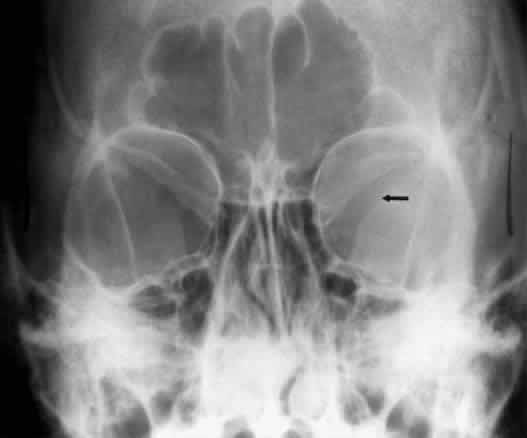

The optic foramen should measure 6 mm vertically and 5 mm horizontally. Asymmetry greater than 1 mm or a vertical dimension greater than 6.5 mm is considered abnormal.15,27 Ninety-eight percent of patients have optic canals that vary by less than 1 mm.27 Concentric enlargement of the foramen and optic canal can be seen with optic nerve gliomas, meningiomas, neurofibromatosis, and less commonly an aneurysm of the ophthalmic artery (Fig. 16). A decrease in the optic foramen and canal dimension can be seen in fibrous dysplasia, Paget's disease, hyperostosis secondary to a meningioma, or microphthalmos (Fig. 17, Table 1).

Fig. 16. Oblique apical projections showing the optic foramen. The left optic foramen has concentric enlargement from an optic nerve glioma. The foramen should not have greater than 1 mm of asymmetry.

Fig. 17. Bilateral optic canal compression from fibrous dysplasia. There is diffuse bone thickening in each orbit. Note small size of optic foramen (arrow).